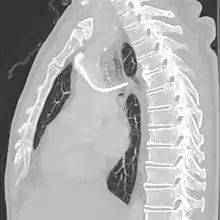

After the entry site is punctured with ultrasound, a guidewire is inserted with the tip of the guidewire reaching the inferior vena cava. The proximal end of the guidewire is secured to prevent dislodgement. Then a chemoport pocket is created on the deltopectoral region at 2.5 cm below the level of clavicle by using a scalpel. Bupivacaine with adrenaline (0.25%) is used as local anesthetic to reduce the formation of haematoma and prolong the anesthetic effect. After the pocket is created, a trocar is used insert a silicone catheter from the pocket towards the internal jugular vein puncture site. A peel-away sheath is then inserted to facilitate the insertion of the silicone catheter into the cavoatrial junction. Silicone catether insertion should be done during breath hold at inspiration. The peel-away sheath should be pinched to prevent air embolism. The proximal end of the catheter is connected to the port within the skin pocket later after irrigation of the pocket with normal saline.[3]

The port is then sutured on two sites to the underlying muscles. The tip of the catheter is checked for kinks and position using a fluoroscope. Besides that, aspiration of blood and contrast injection through the chemoport can also be used to confirm the position. The port is the closed in two layers (subcutaneous tissue is sutured first, followed by the skin). Sterile dressing is then placed on the port.[3] The optimum site to park the tip of the catheter is at the cavo-atrial junction or with margin of error of not more than 4 cm above the junction.[3]

The incidence of catheter fracture is 2.3%. The fracture can be due to "pinch-off syndrome" when the vein and the catheter is compressed when passes between the clavicle and first rib before turning 90 degrees into the superior vena cava. Fractured catheter component can dislodge most commonly into pulmonary arteries (35%), right atrium (27%), right ventricle (22%), and superior vena cava and peripheral veins (15.4%).[5]